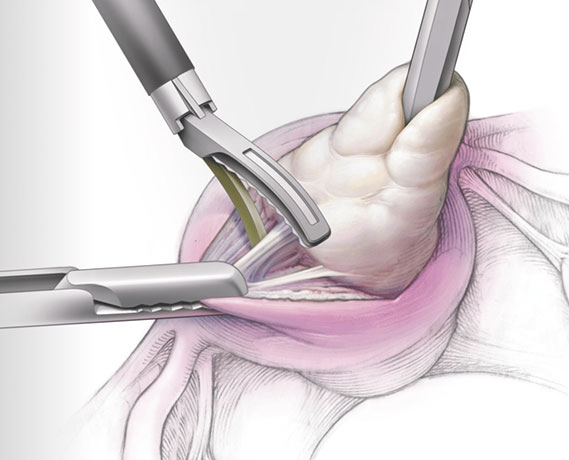

Myomlar, genellikle tedavi gerektirmezler fakat hastada aşırı kanama, anemi, ağrı ya da gebeliğe engel durum oluşturuyorlarsa cerrahi olarak çıkarılmaları gerekir.

- Laparoskopik Ameliyatlar

- Histeroskopik Ameliyatlar

- Miyom Ameliyatı